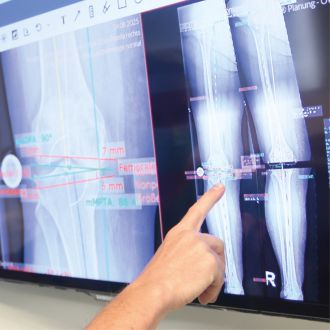

Dank roboterassistierter Kniechirurgie lassen sich Implantate besonders präzise einsetzen und die Funktion des Gelenks nachhaltig verbessern.